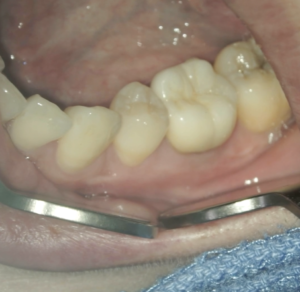

Post-op 1yr Endo test(2026.1.20)

術前の臨床症状は消失した。

外科の切開線の痕もない。

まさに完治だ。